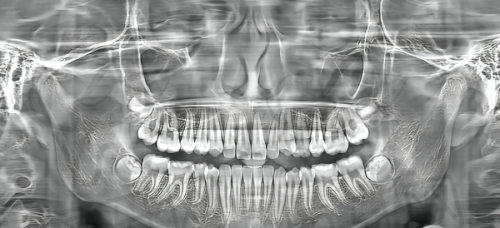

2. 全景 X 光机:全景 X 光机可以拍摄整个口腔的全景图像,让医生全方面了解患者的牙齿和颌骨情况。它可以用于牙齿矫正、口腔疾病诊断等多个方面,为医生提供重要的诊断依据。